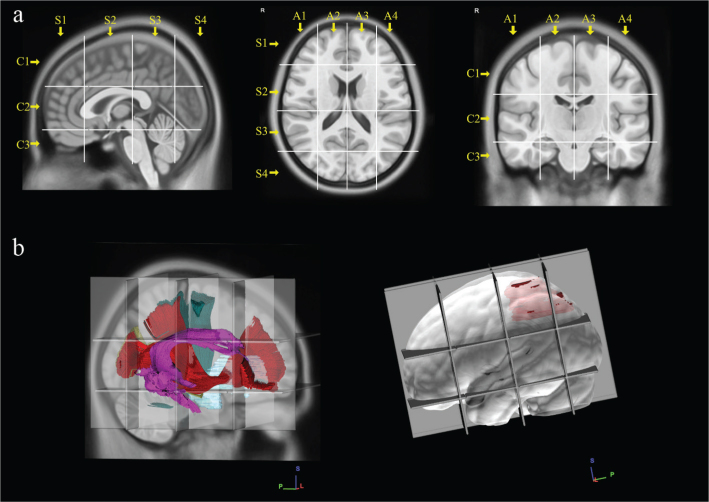

Methods: A series of confirmed WHO 2 astrocytoma patients (between 2005 and 2015) were retrospectively analyzed. MRI sequences (FLAIR) were used for tumor volume segmentation and to create a frequency map of their locations into the Montreal Neurological Institute (MNI) space. The Brain-Grid (BG) system (standardized radiological tool of intersected lines according to anatomical landmarks) was used as an overlay for infiltration analysis of each tumor. Long-term follow-up was used to perform a survival analysis.

Results: Forty patients with confirmed IDH status (26 IDH-mutant, IDHm/14 IDH-wild type, IDHwt) according to WHO 2021 classification were included with a mean follow-up of 7.8 years. IDHm astrocytomas displayed a lower number of BG-voxels (P < 0.05) and were preferentially located in the anterior insular region. IDHwt group displayed a posterior insular and peritrigonal location. IDHwt group displayed a shorter OS compared with IDHm (P < 0.05), with the infiltration of 7 or more BG-voxels as an independent factor predicting a shorter OS.